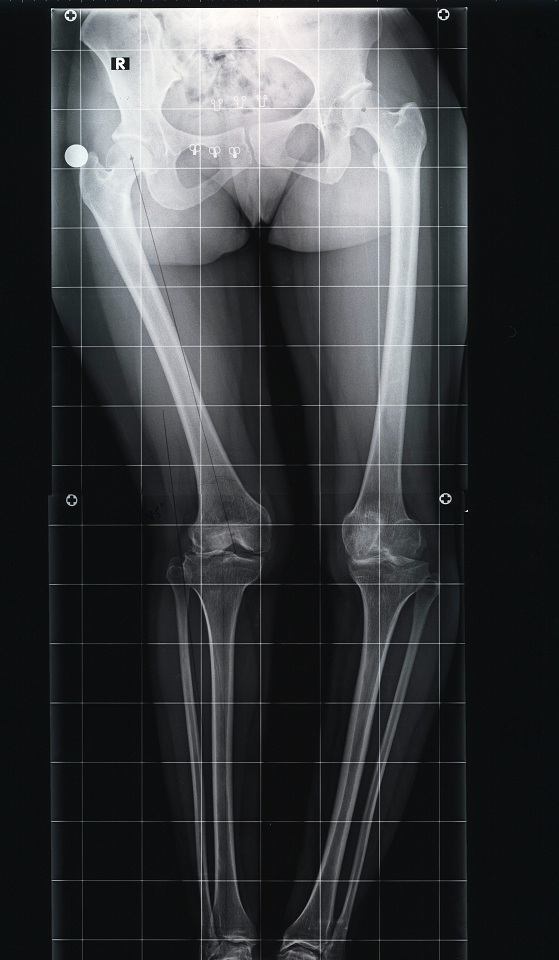

arthritis deformity surgery endoprosthesis hip prosthesis ilizarov ilizarov surgery infected nonunion knee prosthesis lengthening surgery limb lengthening surgery nonunion periprosthetic infection psodoartroz revision surgery total hip prosthesis total knee prosthesis